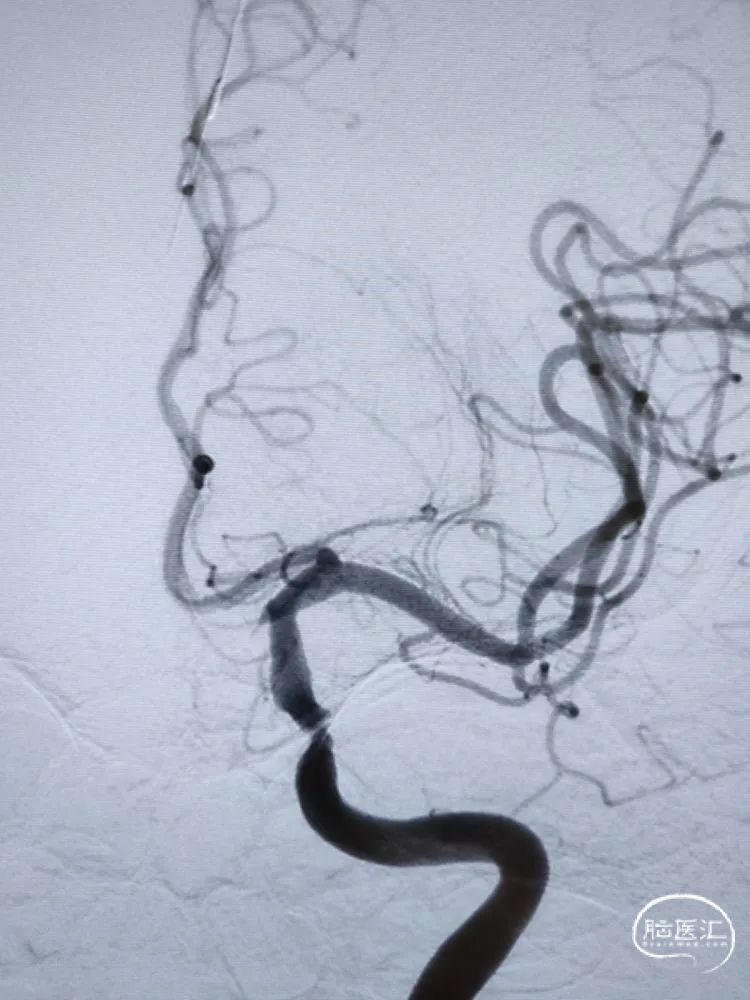

DSA检查:全脑血管造影检查提示左侧颈内动脉海绵窦段-水平段中段重度狭窄。

DSA检查:远端正常段管径约3.22mm,近端接近正常段管径约4.01mm,预估支架长度约12.67mm;合并后交通动脉圆锥。